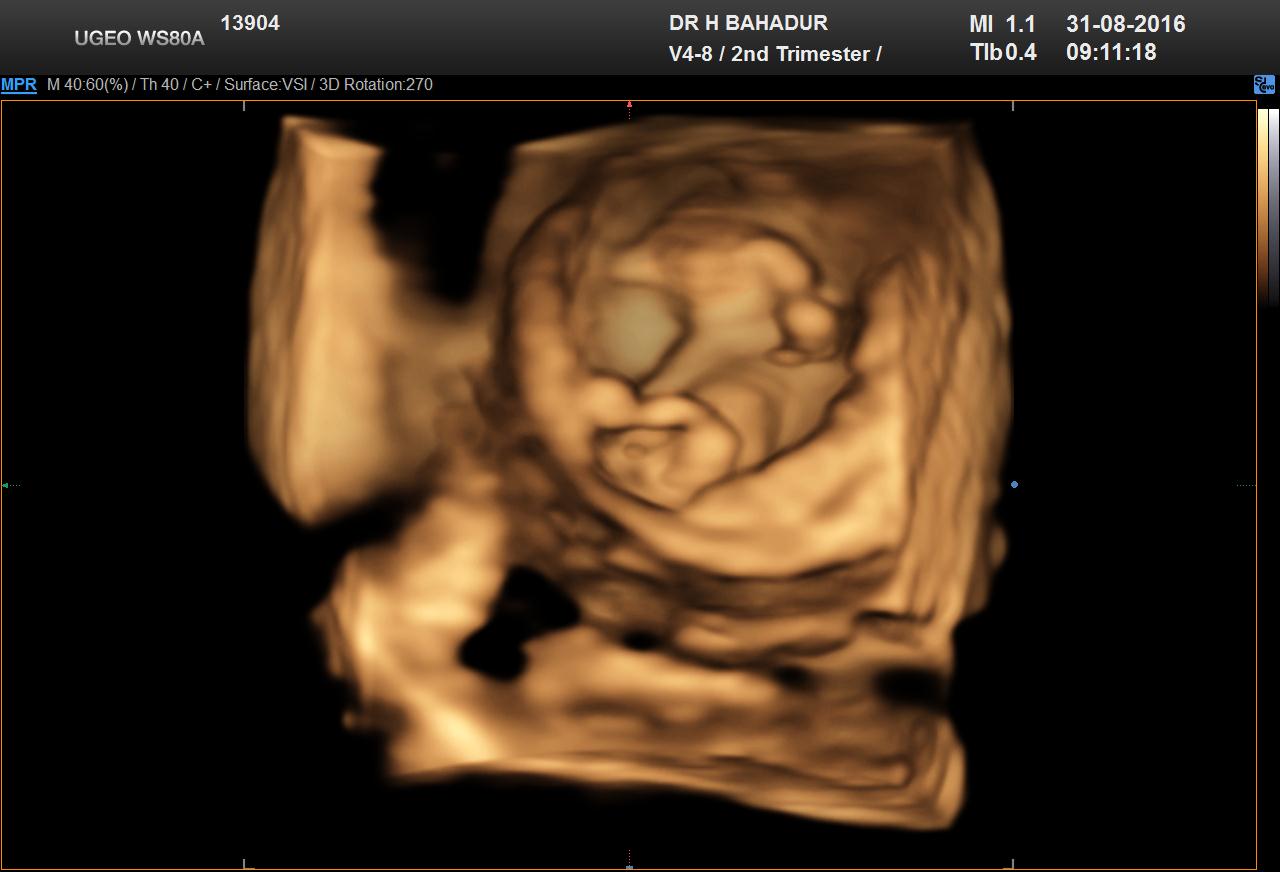

Girl or boy nub??? HELP pls any guesses

Hi guys. Boy or girl nub??

Attachment 33222